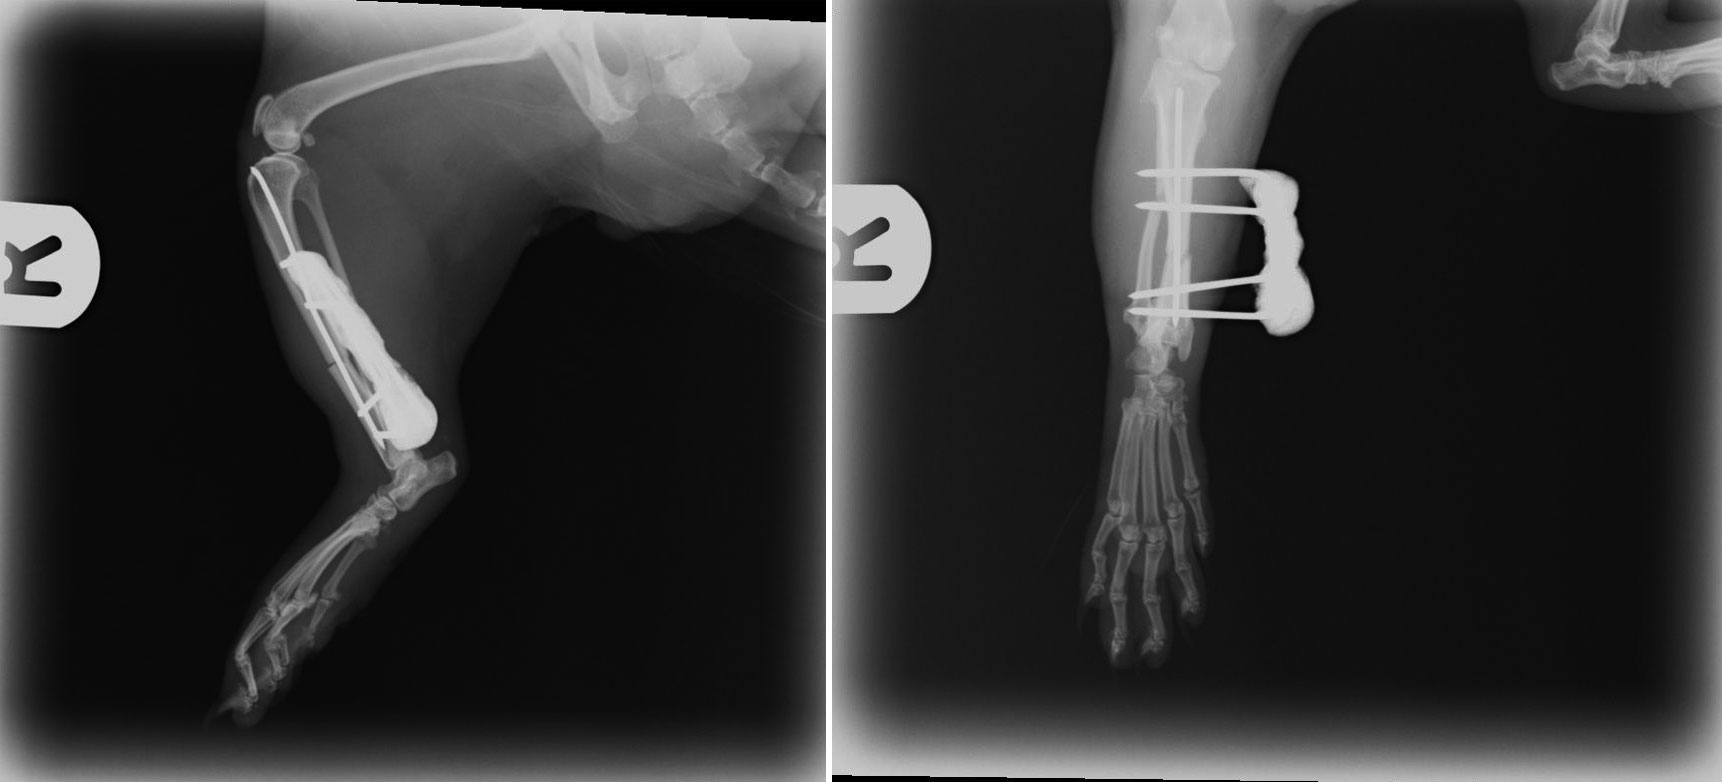

This presented us with quite the challenge because JD’s bones were so tiny. I performed an extremely fiddly operation to fix his bones back together again. Below you can see the x-rays we took after the operation - the white lines are tiny 1mm wide pins that are holding the two ends of bone together whilst the body heals them. The operation went extremely well and JD should make a full recovery.